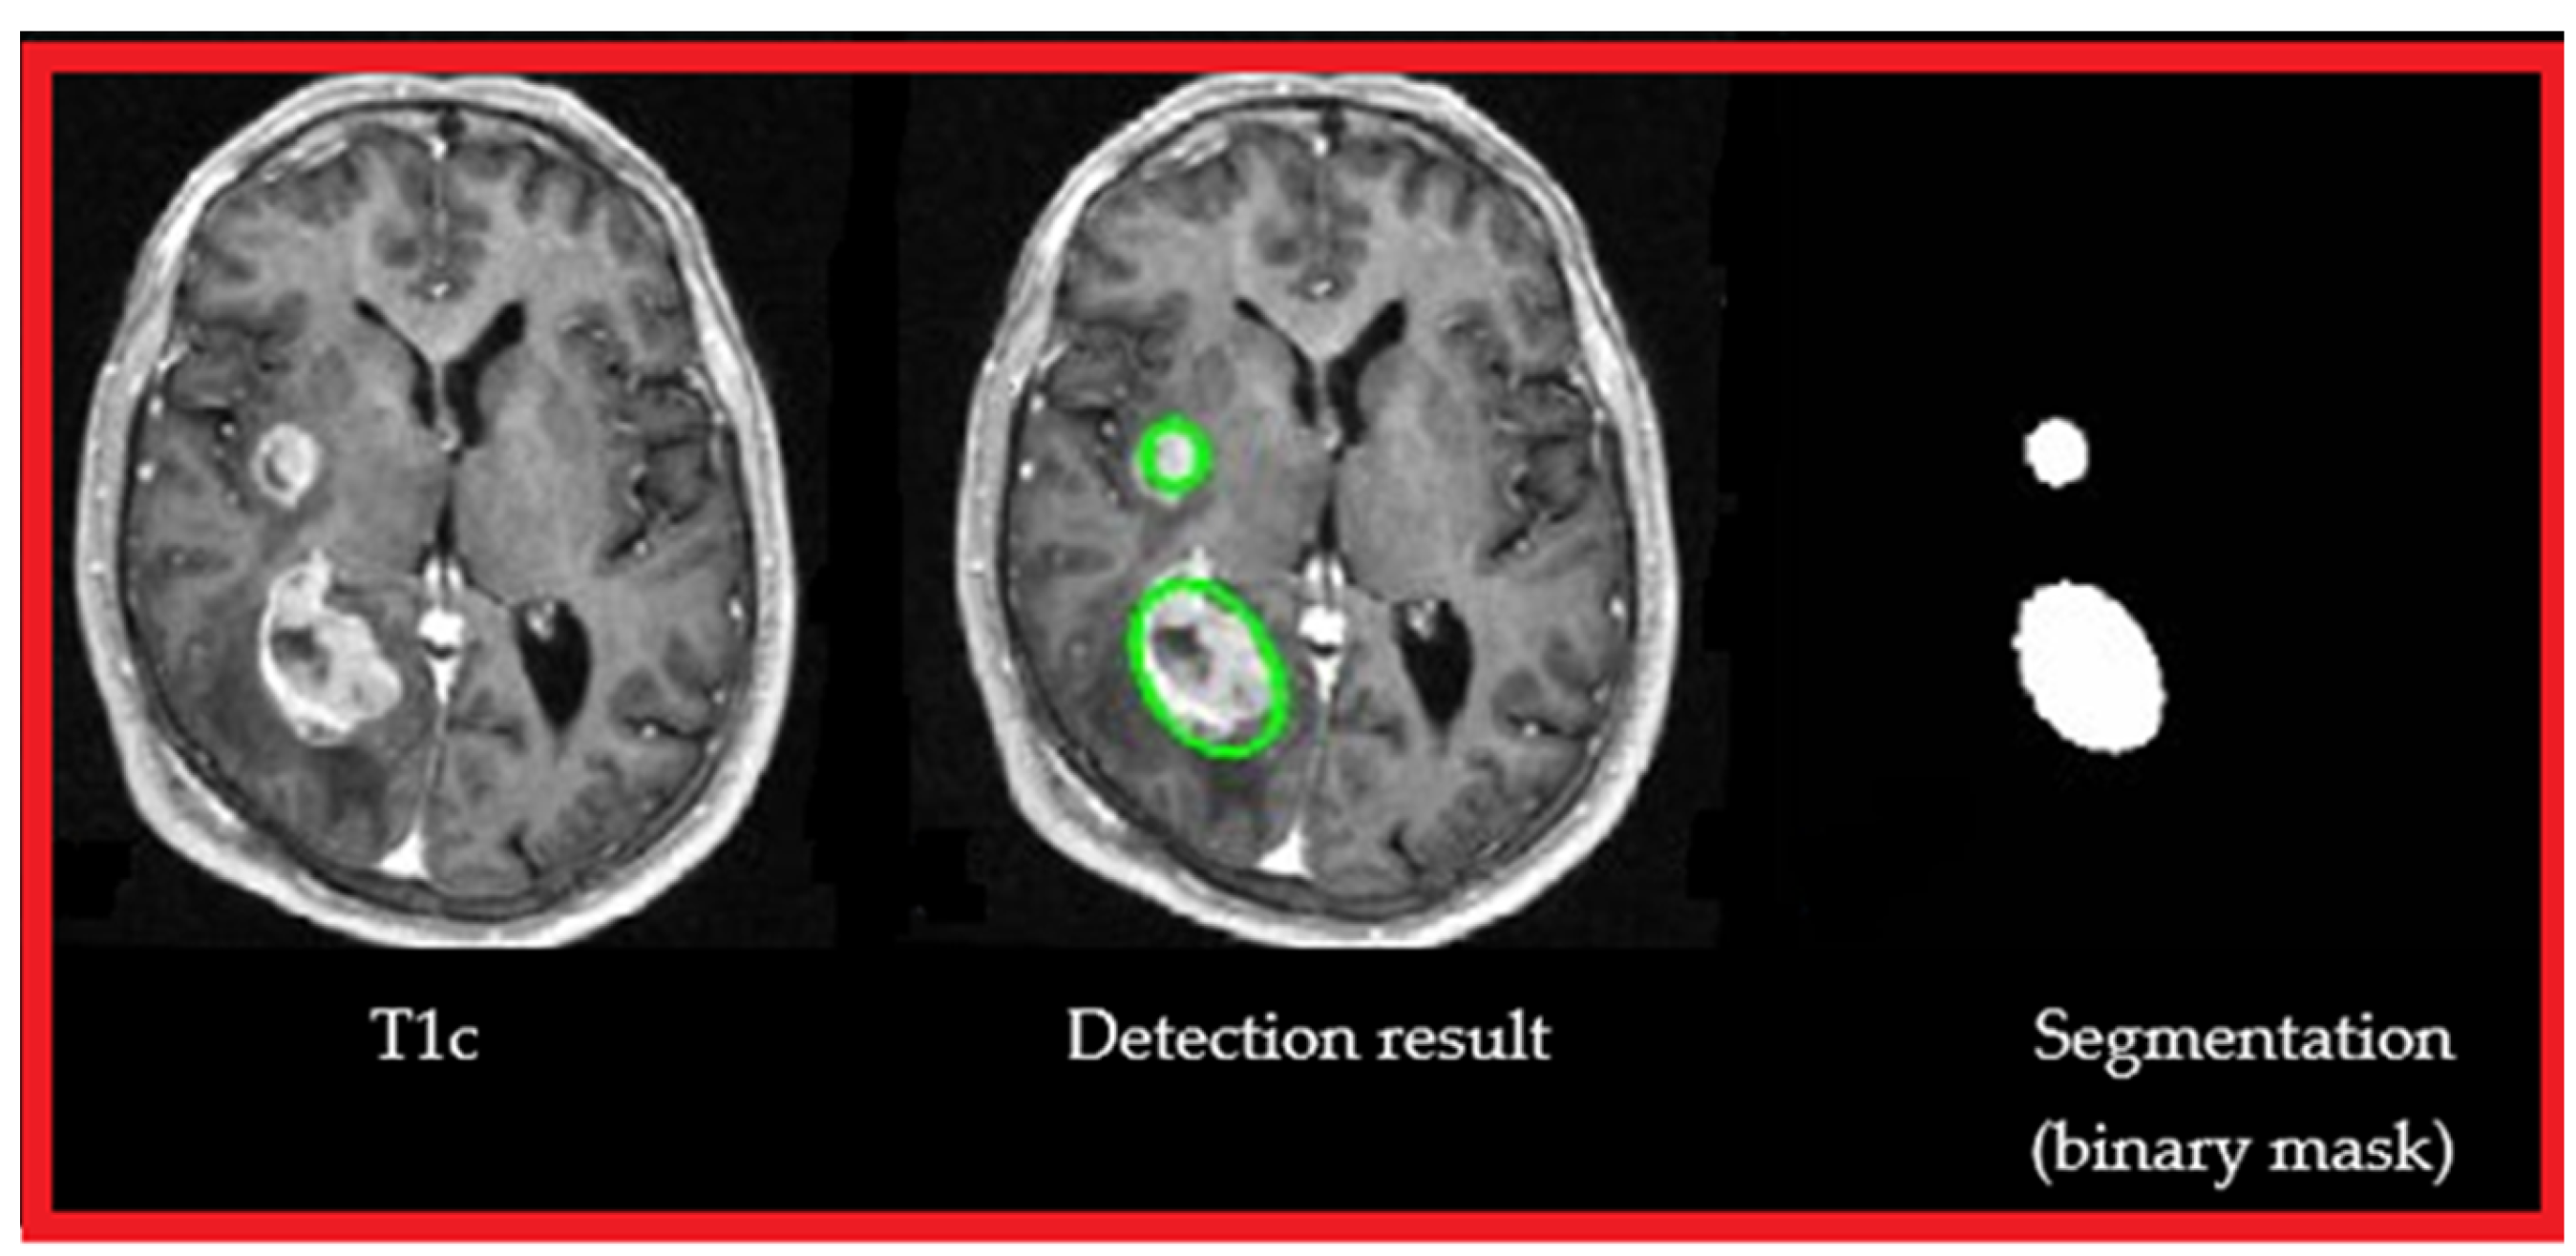

3.2. ROI Detection

4.1.2. Experiments

- A.

- Experiment #1